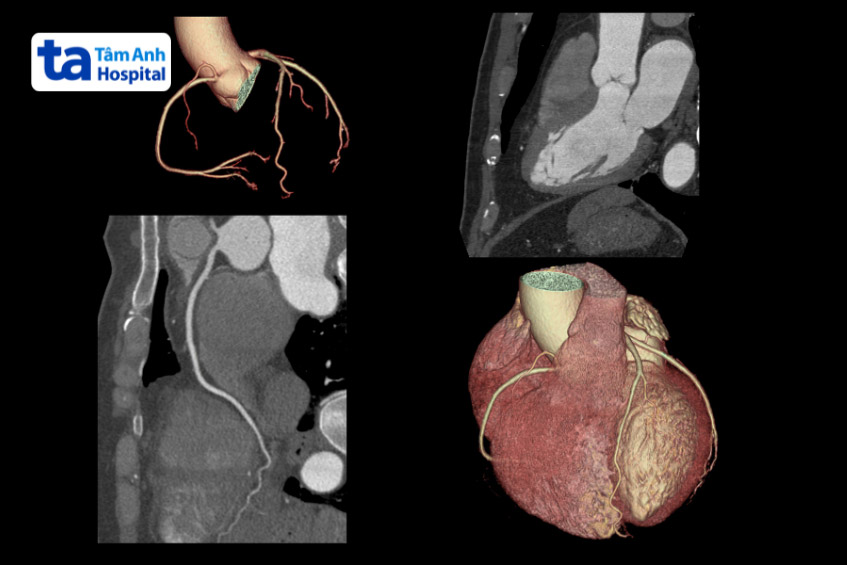

Mạch vành có hai động mạch vành chính, động mạch vành phải (RCA) và động mạch vành chính trái (LMCA), cả hai đều xuất phát từ gốc động mạch chủ. Động mạch vành trái có nhiệm vụ cung cấp máu cho phần trước và bên tâm thất trái, động mạch vành phải cung cấp máu cho thất phải và phần sau của thất trái. (2)

Hình ảnh giải phẫu mạch vành được minh họa và hiển thị bằng kỹ thuật chụp CT, giúp bác sĩ quan sát rõ hơn về cấu tạo của mạch vành.

Động mạch vành nằm ở vị trí xung quanh và bên trong cơ tim. Chúng phân nhánh từ động mạch chủ, là động mạch chính trong cơ thể.